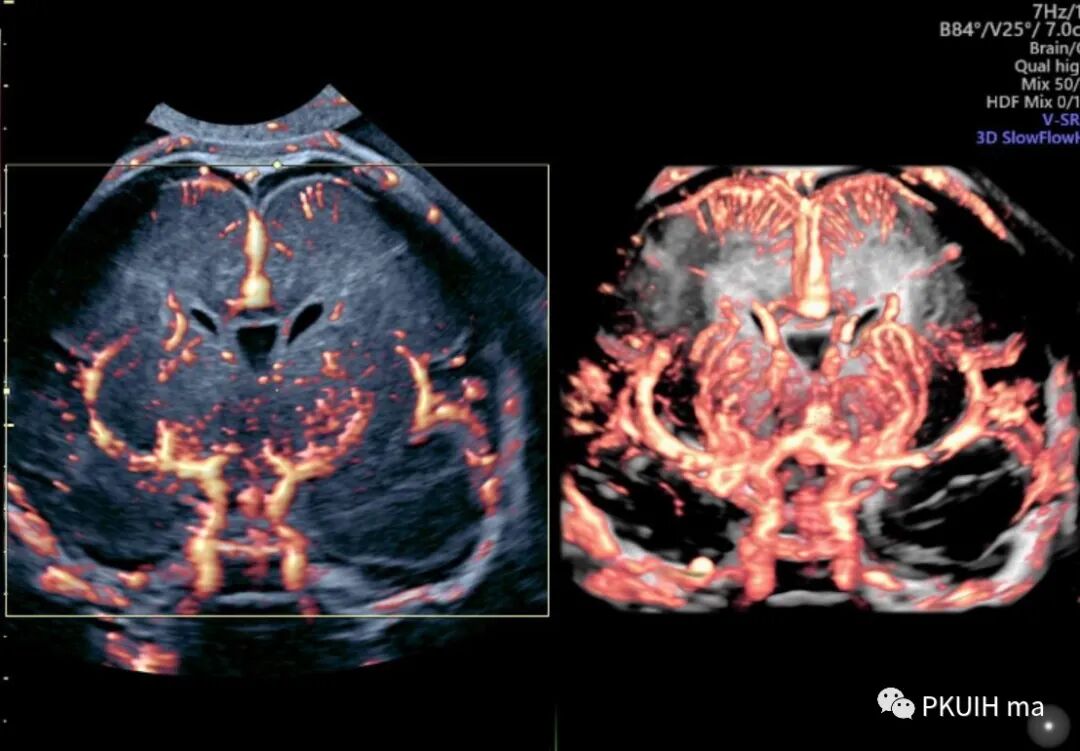

同样我们可以利用容积血流成像来显示颅底动脉环,看着更有立体感,但效果不如SlowFlow功能